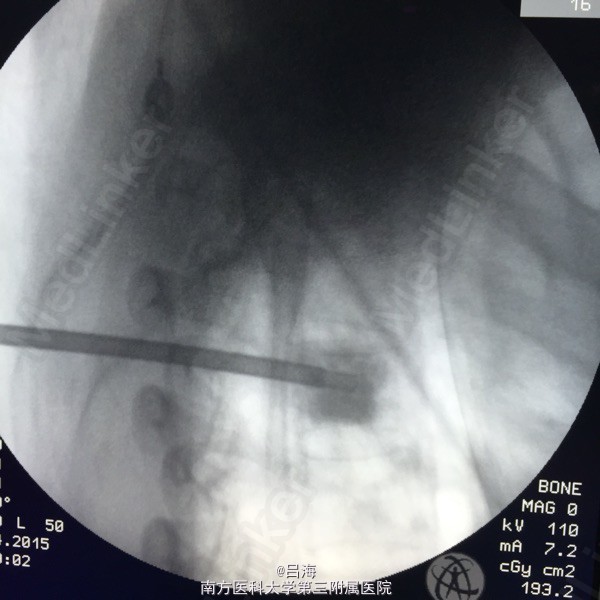

胸4椎体血管瘤 局麻下行经皮活检,椎体成形术

患者背痛并左肋部症状明显缓解,术后第二天出院。 椎体血管瘤多数可不手术,但如患者椎体破坏严重,症状进行性加重,这可考虑手术治疗